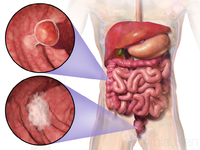

سرطان القولون والمستقيم

مقالة مفصلة: سرطان القولون والمستقيم

مقالة مفصلة: سرطان القولون والمستقيم

| سرطان القولون والمستقيم | ||

| معدل الانتشار | 9.4 مليون (2015)[7] | |

| معدل البقاء 5 سنوات | 65% (الولايات المتحدة)[4] | |

| حالات الوفاة | 832.000 (2015)[6] | |

| عوامل الخطورة | التاريخ العائلي لحدوث سرطان القولون والمستقيم في الأسرة؛ سلائل (پوليپات) polyps أو أمراض الأمعاء الالتهابية. تم ربط وجود طفرات جينية نوعية بداء السليلات الغدومي العائلي familial adenomatous polyposis (الذي يمكنه أن يتحول إلى سرطان القولون) وبسرطان القولون والمستقيم الوراثي غير السليلي. ويزداد خطر الإصابة أيضا عند الذين يعيشون في المدن أو المناطق الصناعية. وتتضمن بقية عوامل الخطورة نقص النشاط البدني والتعرض لمواد كيميائية معينة وتناول الأغذية الغنية بالدهون أو قليلة الألياف. | |

| العلامات المنذرة | وجود دم في البراز؛ أيُّ تغيرٍ في عادات التغوط؛ انزعاج معدي عام، فقدان وزن ليس له ما يبرره. | |

| الكشف والتشخيص | يجب إجراء فحص المستقيم بالإصبع وتحرّي الدم في البراز سنويا لكل شخص يفوق الأربعين عاما؛ تنظير السيني sigmoidoscopy كل 3 ـ 5 سنوات بعد سن الخمسين. وإذا اشتُبِه بوجود أي اضطرابات، يمكن إجراء تنظير القولون واستخدام رحضة (حقنة) الباريوم barium enema (للتمكن من رؤية الأمعاء عند التصوير بالأشعة السينية). ويكون الإنذار prognosis سيئا إذا كانت الأمعاء مسدودة أو مثقوبة أو كانت مستويات مواد واسمة marker substances معينة (مثل المستضد الجنيني السرطاني carcinoembryonic antigen والمستضد الكربوهيدراتي 9-19) في مصل الدم مرتفعة قبل العلاج.

| |

| العلاج | الجراحة لإزالة الورم، وأحيانا يضاف إليها المعالجة الشعاعية أو الكيميائية أو كلتيهما. وقد يتحتم في بعض الحالات فَغْر القولون colostomy (عمل فتحة تصريف فيه). وإذا انتشر المرض إلى العقد اللمفاوية، تصبح المعالجة الكيميائية بالفلوروراسيل fluorouracil مفيدة. وبالنسبة لسرطان المستقيم المتقدم والمتوسط الشدة تستخدم المعالجة الكيميائية المترافقة مع المعالجة الشعاعية، ولعل إزالة النقائل من الكبد جراحيا تطيل بُقيا بعض المرضى.

| |

| ملاحظات | ||